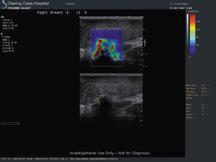

At RSNA 2015, Matthew Ernst, marketing segment manager with Hitachi, introduced Sofia, an automated breast tomography ...

April 14, 2010 - New algorithms for breast ultrasound (US) are making waves in the breast imaging community, which has ...